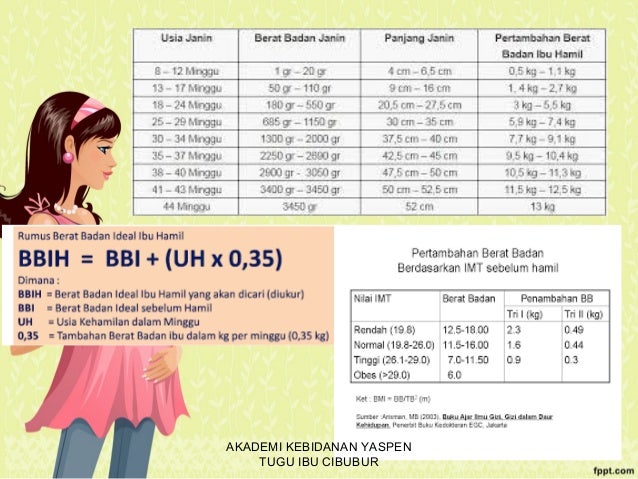

Diagnosa Kehamilan

Diagnosa Kehamilan